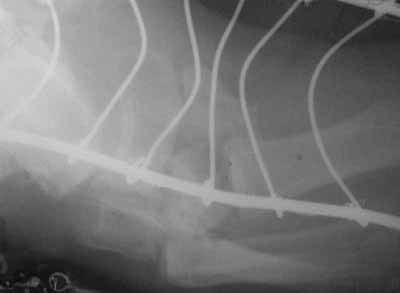

35-year-old male patient was injured falling from height. Among different injuries he acquired a complex foot trauma (fractures of metatarsus and tarsus bones, dislocations of Lisfranc and Chopart joints). Closed reposition and fixation with plaster were carried out.